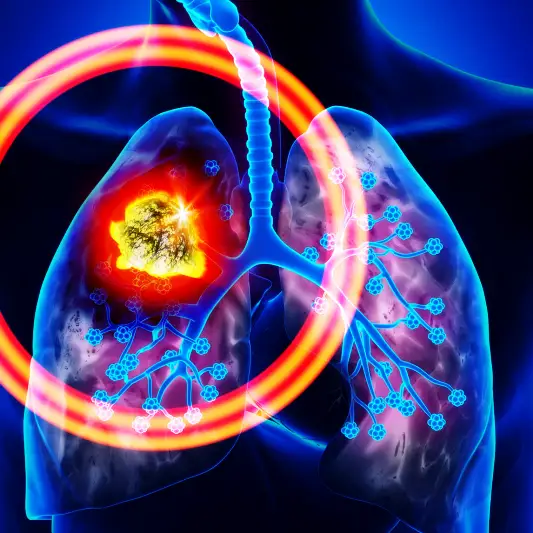

활동 수준 조절 및 운동은 폐암 수술후 필요한 중요한 관리 사항입니다. 수술 후 적절한 활동 수준을 유지하고 자주 활동하는 것이 중요합니다. 하지만 너무 과도한 운동은 피해야 합니다. 적절한 신체 활동은 회복을 촉진시키고 폐 기능을 향상시키는 데 도움이 됩니다.

폐암 수술을 한 환자는 수술 이후에 약간의 휴식이 필요할 수 있습니다. 그러나 지나친 휴식은 근력 감소와 폐 기능을 악화시킬 수 있습니다. 따라서 적절한 운동이 중요합니다. 폐 기능을 향상시키기 위해 걷기나 자전거 타기와 같은 유산소 운동을 꾸준히 실시하는 것이 좋습니다.

운동을 할 때에는 자신의 체력과 피로도를 잘 파악해야 합니다. 너무 과도한 운동은 오히려 회복에 방해가 될 수 있습니다. 운동을 할 때에는 천천히 시작하고 체력에 맞게 조절하는 것이 중요합니다. 특히 수술 후 특정 동작이나 활동에 따른 피로도나 불편함이 있다면 적절히 조절해야 합니다.

활동 수준 조절은 폐암 수술후 정말 중요한 부분입니다. 꾸준한 운동과 적절한 휴식을 통해 회복을 도모하고 건강을 유지할 수 있습니다. 폐암 수술후 관리와 후송 기간동안 이러한 사항들에 유의하여 좋은 결과를 얻을 수 있기를 바랍니다.